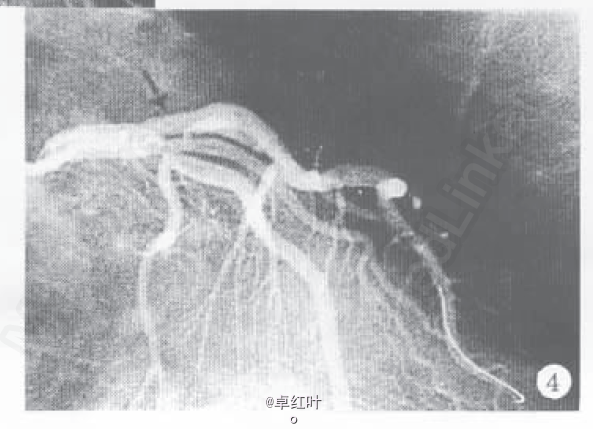

诊断:冠心病,陈旧下壁心肌梗死,劳累恶化型心绞痛; 处理:冠脉造影+支架植入术。

随访术后未再出现胸痛,随访4个月患者未再发作心律失常。 讨论:,对于有器质性心脏病的患者(尤其为冠心病)出现分支型室速,不要笼统认为是良性心律失常,从而不予特殊诊治,因为也可能会导致室颤以至死亡。应给予抗心律失常治疗,更应针对基本病因进行彻底治疗。 DOI:10.3969/j.issn.0253-9896.2000.05.028